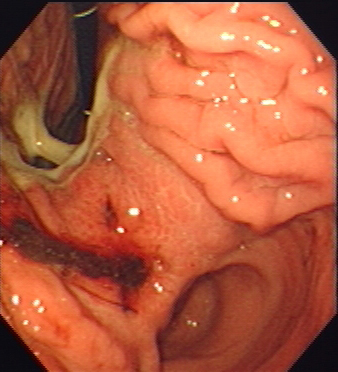

Outpatient Endoscopy